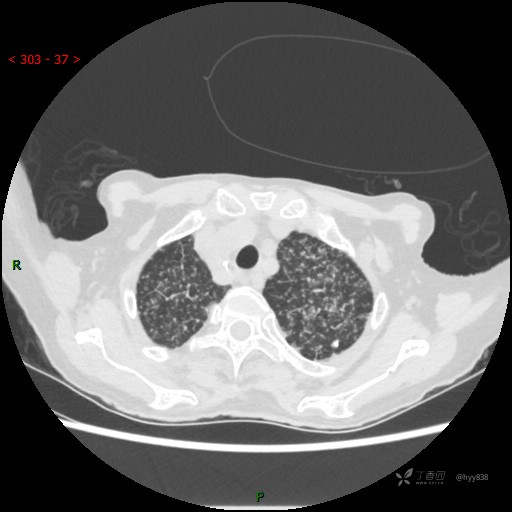

肺部弥漫性、疑难病变,感染或肿瘤?一元论或二元论?贴贴精彩---结果公布~

患者性别:女

患者年龄:73岁

主诉:反复发热10余天

简要病史:患者10余天劳累后出现发热,最高体温达39.5℃,无畏寒、寒战、鼻塞、流涕,无头晕、头痛,无心慌、胸闷、胸痛,无咳嗽、咳痰、气喘,无反酸、烧心、恶心呕吐,无腹痛、腹胀等不适,于2022-5-31至当地中医医院住院治疗,诊断为重症肺炎,予以抗感染、抗病毒等对症支持治疗,仍反复发热,现为求进一步诊治,至我院门诊就诊,门诊以“重症肺炎”收入我科。 起病以来,患者精神、饮食、睡眠差,大小便正常,体力下降,体重无明显变化。

体格检查:T 38℃ P 102次/分 R 17次/分 BP 142/85mmHg,SPO2 84%(未吸氧)。神志清楚,呼吸稍急促,查体合作,咽部充血,未见明显脓点,颈软,全身皮肤黏膜及巩膜未见黄染,浅表淋巴结未触及肿大。双肺呼吸音粗,未闻及明显干湿啰音,HR 102次/分,律齐,各瓣膜区未闻及病理性杂音。腹部平坦,腹软,无压痛,肝脾肋下未触及肿大。双下肢轻度水肿。生理反射存在,病理征阴性。

临床诊断:重症肺炎

胸部CT平扫